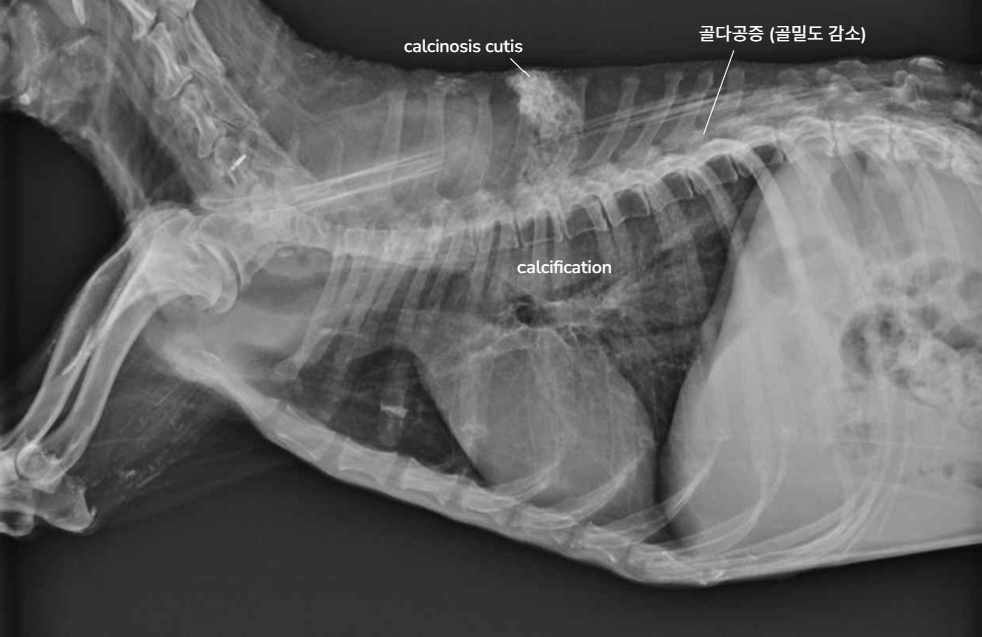

| Radiography (Abd.) - Excellent abdominal detail - Hepatomegaly - Distention of urinary bladder - Cystic calculi - Adrenal mass - Calcified adrenal gland - Dystrophic calcification of soft tissues, calcinosis cutis - Osteoporosis of vertebrae | ![]() |